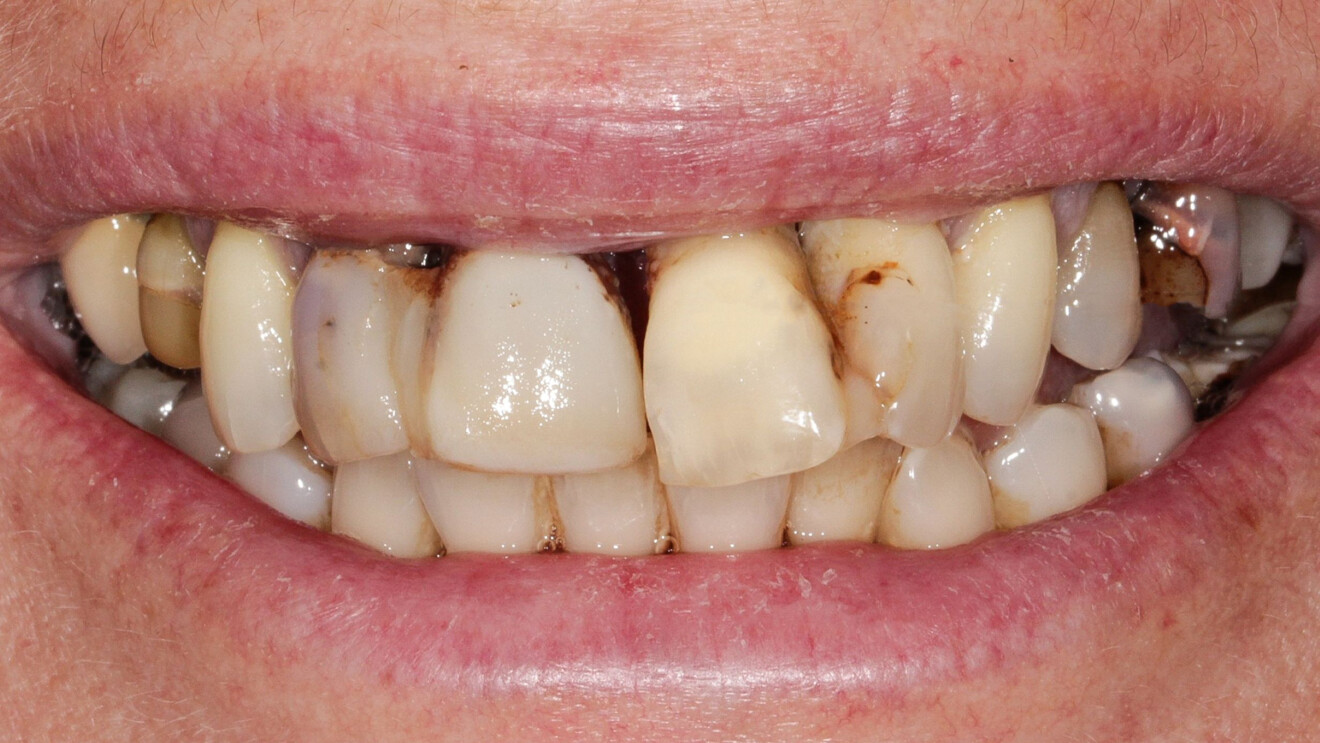

Une patiente de 49 ans nous a été adressée par l’un de nos confrères pour le remplacement de ses quatre incisives maxillaires (Fig. 23). Dans un contexte parodontal avancé, ses incisives centrales présentent une mobilité terminale (classe IV) elle n’ose plus les brosser de peur de les perdre lors de la manoeuvre. La patiente ne présente pas de problèmes de santé particuliers.

À l’examen, on observe une mobilité des quatre incisives maxillaires, une insuffisance osseuse verticale et horizontale, associées notamment au niveau de 11 et 21, la présence de plaque, de tartre et d’inflammation gingivale, surtout au niveau du bloc antérieur maxillaire. On note également la présence d’une dent de sagesse (dent 18) perdue (Figs. 24–26).